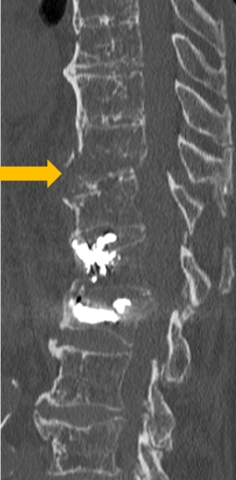

Fig 1 : Fracture de T11 instable sur rachis enraidi chez un patient de 92 ans ostéoporotique (flèche). Antécédent de cimentoplastie de L1 et L2.

Le Pr Catherine Cyteval, spécialiste en imagerie ostéo-articulaire, rappellera que les fractures se manifestent souvent par des signes discrets, atypiques, voire trompeurs chez le sujet âgé. L’ostéoporose, les déformations rachidiennes et l’arthrose compliquent encore la lecture des examens. Une vigilance particulière s’impose : suivre attentivement les corticales osseuses dans les trois plans (fig. 1), examiner soigneusement le fenêtrage en parties molles, et recourir à l’IRM au moindre doute. La radiologie interventionnelle, notamment la cimentoplastie, joue également un rôle clé pour favoriser une reprise rapide de l’activité physique et prévenir le syndrome de glissement.